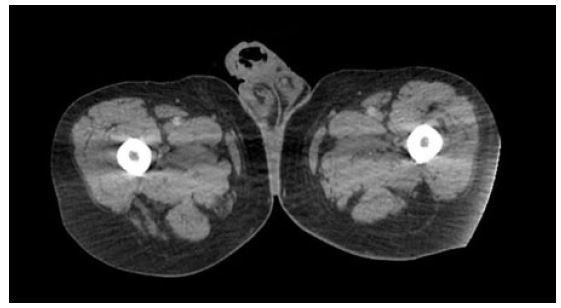

A 58-years-old Saudi male presented with two years history of right painless scrotal mass. There was no history of fever, genital trauma, genital infection, or tuberculosis (TB). The patient denied having nausea, vomiting, diarrhea, flushing, palpitations, or weight changes. On physical examination, the scrotum revealed a right-sided non-tender mass with 2 cm above and not attached to right testis. The left side of the scrotum was normal and no palpable lymph nodes. Normal tumor markers of testicular tumor. Ultrasonography revealed a well-defined, homogeneous, hyperechoic lesion measuring approximately 2 cm in the right extratesticular region.. It was seen superior to right testis and right epididymis and separable from them with high vascularity by Doppler study. Both testes appeared average in size and normal vascularity (Figure 1). Magnetic resonance imaging (MRI) with intravenous (IV) gadolinium contrast for abdominal and pelvis showed right extratesticular soft tissue mass not separable from the spermatic cord and there was no distant metastasis (Figure 2A, Figure 2B, Figure 2C). Based on images, provisional clinical diagnosis of a benign paratesticular mass was made and the patient underwent exploratory excision of the mass with preservation of cord and testis. The patient was discharged two days after surgery. Histopathology showed grossly a single soft gray light brown tissue mass measuring 2×2 cm with white firm focally fleshy cut surface. Microscopically, cells arranged in nested and trabecular growth pattern. The neoplasm is composed of tumor nests comprising of round cells with abundant granular eosinophilic-basophilic focally clear cytoplasm surrounded by sustentacular cells embedded in vascular rich stroma. The lesion exhibited no evidence of capsular invasion, lymphovascular invasion, a diffuse pattern, tumor necrosis, atypical mitosis, or increased mitotic activity. Histopathology reported this mass is paraganglioma.

Figure 1: Ultrasonography showed homogeneous hyperechoic lesion measuring approximately 2 cm.